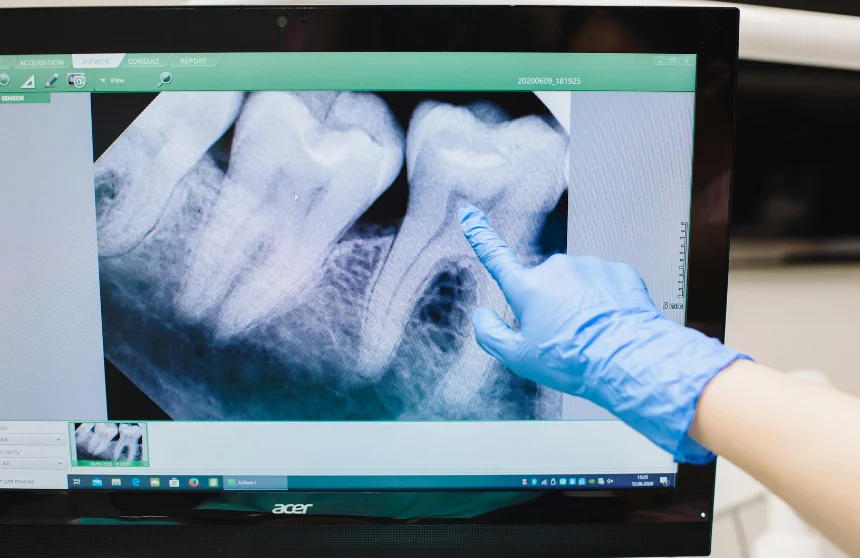

Consultation: A thorough examination and X-rays determine

the condition of your wisdom teeth.